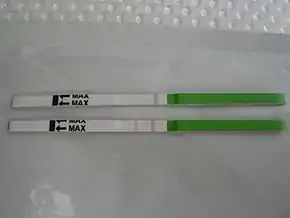

Predicting ovulation

The detection of a surge in release of luteinizing hormone indicates impending ovulation. LH can be detected by urinary ovulation predictor kits (OPK, also LH-kit) that are performed, typically daily, around the time ovulation may be expected.[31] A conversion from a negative to a positive reading would suggest that ovulation is about to occur within 24–48 hours, giving women two days to engage in sexual intercourse or artificial insemination with the intention of conceiving.[32]

The recommended testing frequency differs between manufacturers. For example, the Clearblue test is taken daily, and an increased frequency does not decrease the risk of missing an LH surge.[33] On the other hand, the Chinese company Nantong Egens Biotechnology recommends using their test twice per day.[34] If testing once per day, no significant difference has been found between testing LH in the morning versus in the evening, in relation to conception rates,[35] and recommendations of what time in the day to take the test varies between manufacturers and healthcare workers.[36] Tests may be read manually using a color-change paper strip, or digitally with the assistance of reading electronics.

Tests for luteinizing hormone may be combined with testing for estradiol in tests such as the Clearblue fertility monitor.

The sensitivity of LH tests are measured in milli international unit, with tests commonly available in the range 10–40 m.i.u. (the lower the number, the higher the sensitivity).

As sperm can stay viable in the woman for several days, LH tests are not recommended for contraceptive practices, as the LH surge typically occurs after the beginning of the fertile window.